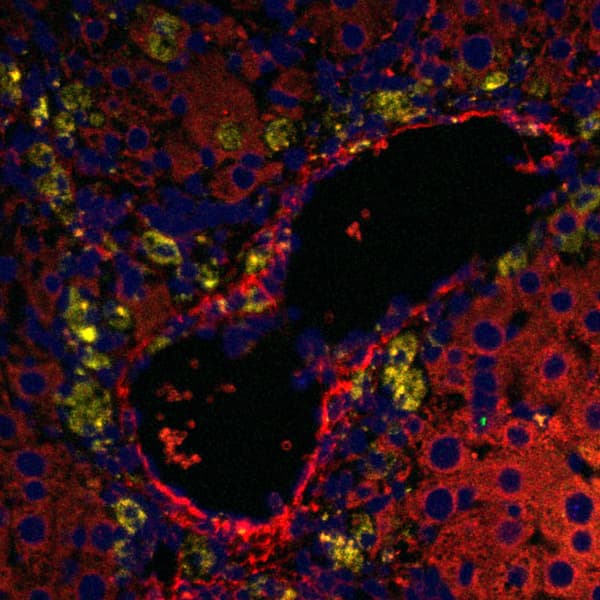

WT mouse liver showing movement of blood through sinusoidal vessels (Texas-Red) and Neutrophils (blue).

SCD mouse liver showing vasoocclusion at baseline.